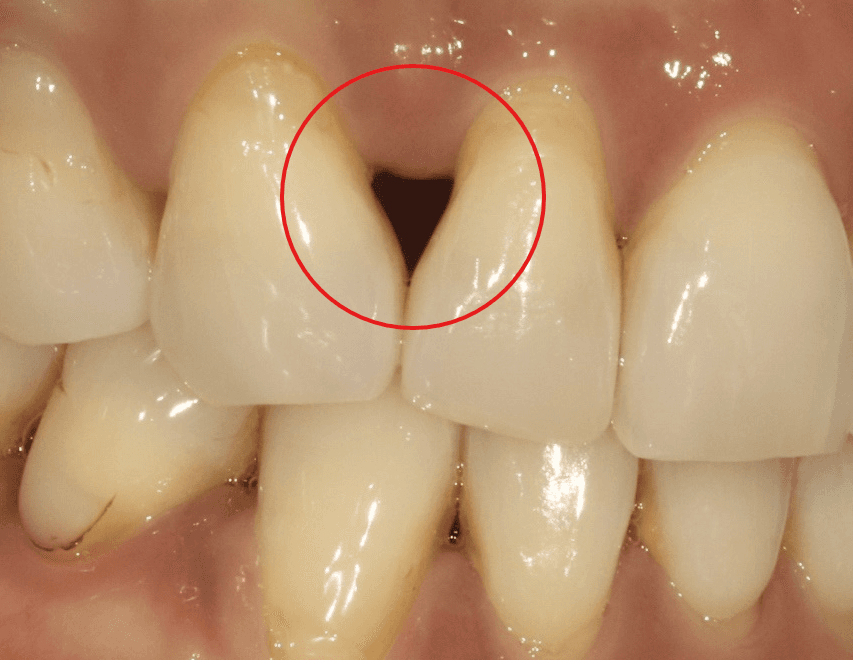

처음에는 크게 눈에 띄지 않았지만, 시간이 지날수록 상악 앞니 두 개 사이에 검은 삼각형 모양의 공간, 즉 '블랙트라이앵글'이 점점 커졌습니다.

블랙트라이앵글(Black Triangle)은 치아 사이 잇몸이 내려가면서 생기는 삼각형 모양의 빈 공간을 말합니다. 주로 다음과 같은 원인으로 발생합니다

교정 후 생긴 블랙트라이앵글, 바이오클리어로 자연스럽게 해결 - 이미지 1